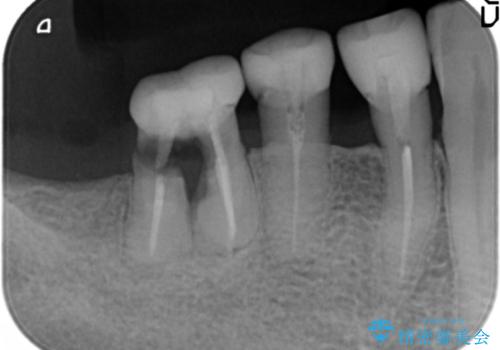

精査したところ、右下の奥歯は大きなう蝕により保存不可能な状態でした。

患者様のご希望により、抜歯後インプラント治療を行いました。

- ¥550,000 (インプラント、骨増生、アバットメント、クラウン) ※税込費用は治療当時の料金となります

奥歯でしっかりと咬むことができるようになり、大変喜んで頂けました。